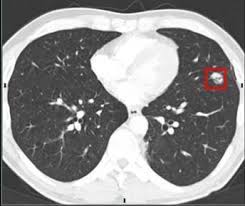

Most lung cancers don't cause symptoms until the disease has advanced, in part because the lungs have few nerve endings. Ct scan showing a cancerous tumor in the left lung. The scan only takes a few minutes and is not painful. Undergoing regular screening may be a good idea for people with a high risk of developing lung cancer. Lung cancer is the leading cause of cancer deaths in males and females in the united states.

Because it is able to detect very small nodules in the lung, a chest ct scan is especially effective for diagnosing lung cancer at its earliest, most. This method of ct scanning builds a detailed image of the body's internal workings. Early detection of lung cancer is being made easier through the use of ct scans. Lung cancer is the leading cause of cancer deaths in males and females in the united states. Around 44,500 people are there are usually no signs or symptoms in the early stages of lung cancer, but many people with if the ct scan shows there might be cancer in the central part of your chest, you'll have a bronchoscopy. This may reveal an obvious mass, the widening of. Most lung cancers don't cause symptoms until the disease has advanced, in part because the lungs have few nerve endings. The scan is painless and takes about 10 to 30 minutes. Ct scan showing a cancerous tumor in the left lung. Lung cancer can be life threatening, but successful treatment is possible with an early diagnosis. Ct scans to find lung cancer in smokers. It is used to look for early signs of lung cancer. Radiological scan is useful in detecting early npc.